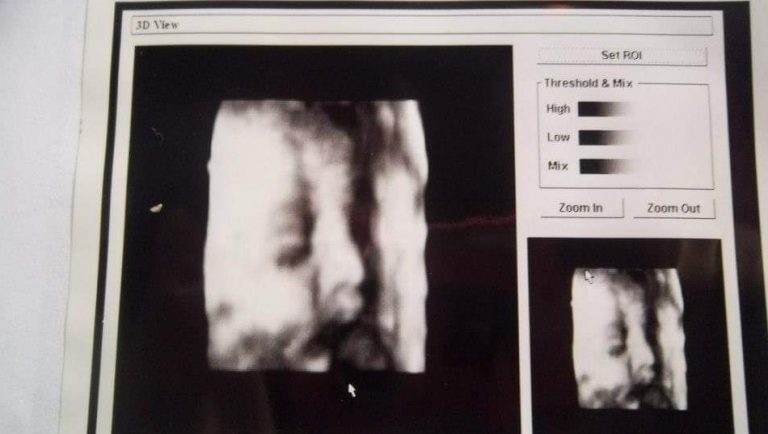

Una gran polémica se generó luego de que una mujer denunciara en su cuenta de Facebook haber recibido la misma ecografía 3D que vio circulando en internet. Tras su mensaje, las denuncias contra el doctor Eduardo Oliva Andaur aumentaron en, al menos 40, las cuales habrían ocurrido en un lapso de cerca de ocho años.

Oliva Andaur parte explicando en el texto que el procedimiento realizado a cada paciente corresponde a ecografías de dos dimensiones. En cambio, la ecografía 3D se realizó solo por petición de los padres que querían conocer de manera anticipada el rostro de su hijo o hija, afirmando que esto no tuvo un fin médico.

Respecto a la razón por la que se entregó a decenas de mujeres la misma imagen, el ginecólogo explica que "de manera involuntaria al momento de imprimir la imagen en 3D, esta correspondía a una foto configurada previamente por el fabricante del equipo a modo de demostración“.

El hombre además aseguró que la fotografía no corresponde al bebé de ninguno de sus pacientes, sino que a una imagen preestablecida. Por lo mismo, el profesional considera que esto lo exime de responsabilidad."No existe engaño alguno de mi parte; así como tampoco hubo cobro adicional por la entrega de la imagen 3D”, agrega.